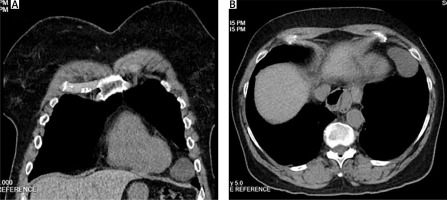

On imaging, computed tomography (CT) revealed a large pericardial cyst measuring 5 cm in diameter (Figure 1). The cyst was confined to the left cardiophrenic angle and was adjacent to the fifth rib along the inner chest wall. Transthoracic echocardiogram was normal with slightly elevated B-type natriuretic peptide.

Figure 1

Computed tomography of the pericardial cyst in the left cardiophrenic angle, coronal (A) and transverse (B) views